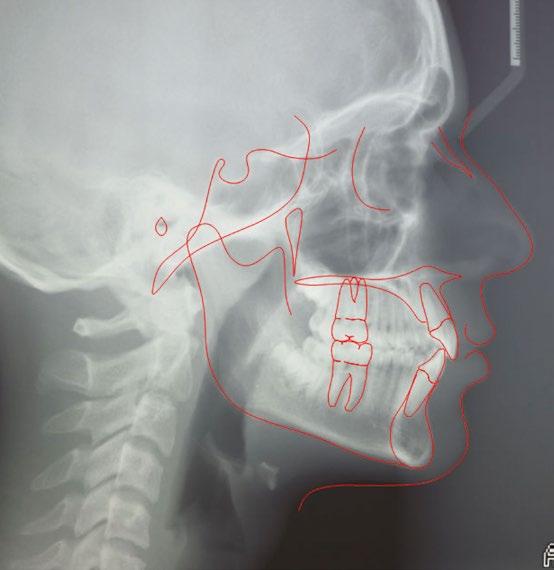

En la ortopantomografía realizada al inicio del tratamiento (Fig. 3) no se observa nada relevante, excepto la presencia de todos los terceros molares en forma de gérmenes dentales. La cefalometría realizada en la telerradiografía lateral (Fig. 4) muestra una clase I esquelética (ANB: 3.1°), en un tipo facial hipodivergente (FMA: 21.5°). El incisivo superior presenta una inclinación reducida con respecto al plano palatal (U1-pp: 105.6°), mientras que el incisivo inferior

está correctamente posicionado con respecto al plano mandibular (IMPA: 95.0°).

3 4

Fig. 4: Tracing cefalométrico realizado en la telerradiografía lateral al inicio del tratamiento.